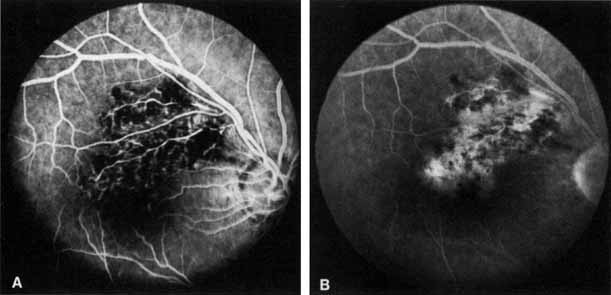

Fig. 2 A. Nonischemic central retinal vein occlusion. Note venous engorgement, dot, blot, and flame-shaped hemorrhages, blurring of disc margins, and a hemorrhage overlying the macula. B. Fluorescein angiogram reveals mild venous engorgement and tortuosity with virtually no capillary nonperfusion.

The ophthalmoscopic features of nonischemic central retinal vein occlusion are similar to those of ischemic central retinal vein occlusion, but are much less extensive (see Fig. 2; Fig. 3A and 3B). Engorgement of the venous tree (including the capillaries) is prominent; there is increased tortuosity and dilation and a darker appearance of the blood column. Retinal hemorrhages vary markedly. Sometimes they occur only peripherally; at other times, they may be rather prominent in the posterior pole.60 Cotton-wool spots are rare. Vision may be decreased because of macular edema or macular hemorrhage.

Fig. 3 A and B. Acute nonischemic central retinal vein occlusion in a 36-year-old hypertensive man. His visual acuity was 20/200. C and D. Six weeks later, he presented with eye pain, decreased vision, and neovascular glaucoma. The type of occlusion now is ischemic.

Fig. 5 Fluorescein angiogram of acute ischemic retinal vein occlusion. Capillary nonperfusion is essentially 100%.